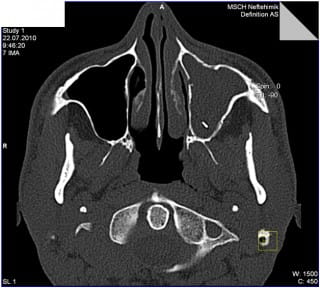

МСКТ придаточных пазух носа

Способность рентген-излучения проникать глубоко в подкожные слои и обнаруживать различные аномалии тканей и органов положена в основу работы мультиспирального компьютерного томографа. Данный метод диагностики нашел широкое применение при изучении заболеваний ЛОР-органов, в том числе – патологий пазух носа. Несложная и безболезненная процедура отражает состояние тканей на снимке, который затем детально расшифровывается. Результаты исследования позволяют подобрать оптимальный курс лечения и отслеживать его эффективность в динамике.

Принцип проведения обследования МСКТ пазух носа – направление рентген-лучей вглубь носовых ходов. Полученное отражение появляется на мониторе. Изменение проекции луча к поверхности тканей дает объемные снимки, на которых будут заметны любые патологии. В числе прочих особенностей МСКТ пазух носа:

отображение состояния носовой полости послойными снимками с толщиной среза менее миллиметра;

возможность обследования пациентов, в теле которых имеются металлические имплантаты и электронные устройства;

для проведения процедуры требуется менее часа;

на снимках можно обнаружить добро- и злокачественные опухоли на любой стадии развития, следы кровоизлияний и прочие симптомы опасных заболеваний;

с помощью 3D снимков можно получить сведения о локализации патологического процесса;

допускается проведение исследования с контрастированием;

низкая доза облучения безвредна для организма.

Благодаря полной безопасности допускается многократное повторение процедуры для исследования состояния пациента в динамике. Применение высокоточного оборудования гарантирует получение достоверных результатов, которые можно использовать как базу для выработки тактики лечения.

Что показывает МСКТ пазух носа

По снимку МСКТ можно уточнить:

• состояние и проходимость слезных протоков;

• повреждения и аномалии костной ткани;

• присутствие в пазухах инородных тел, скопления жидкости и прочих патологий;

• наличие кист, новообразований, полипов и т.д.

Качественный снимок МСКТ дает исчерпывающую информацию в разрезе предварительного диагноза и его детализации, указанной в назначении.